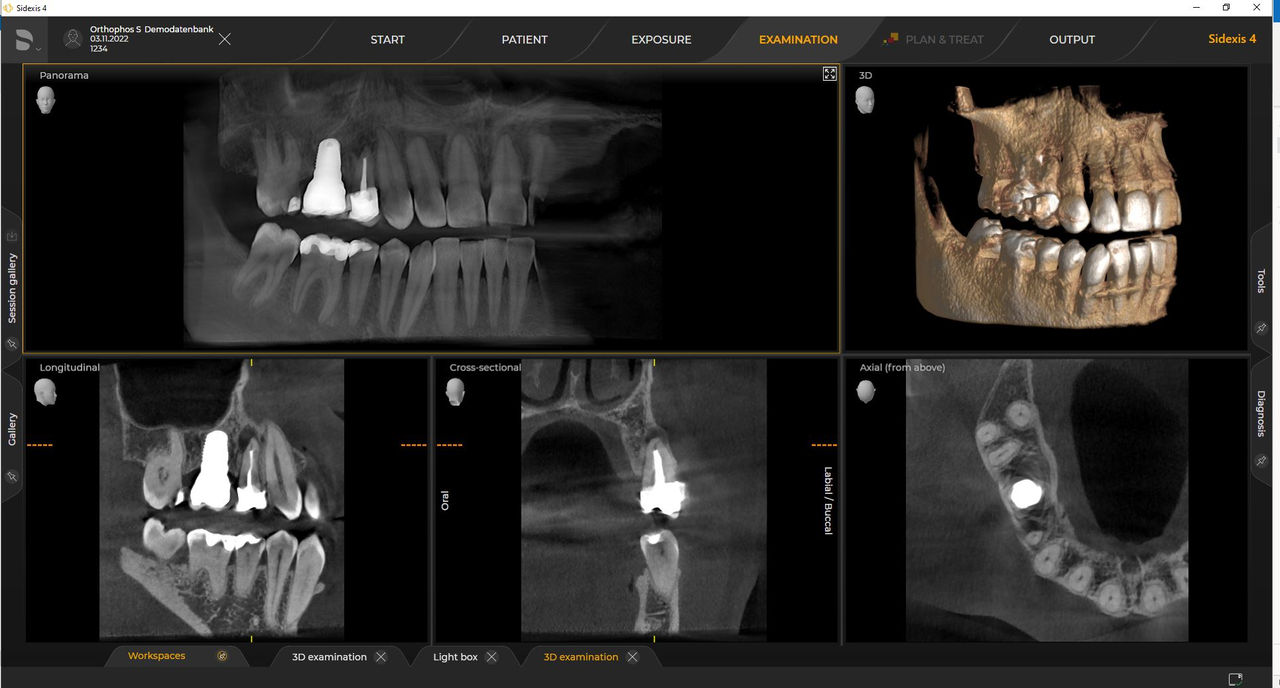

Con el modo de dosis baja inteligente 3D, obtiene imágenes 3D en el rango de dosis de una imagen radiológica 2D. En el modo HD (hasta 1400), las imágenes individuales se obtienen durante una única rotación y se convierten en un volumen 3D con hasta 80 μm para imágenes de bajo ruido en alta resolución.

Una amplia gama de tamaños de volumen para satisfacer sus diversas necesidades clínicas y de diagnóstico, desde Ø 5 x 5,5 cm hasta Ø 11 x 10 cm

Las unidades de radiología de Dentsply Sirona funcionan exclusivamente con Sidexis 4. Sin embargo, la migración de datos de Sidexis XG a Sidexis 4 es muy fácil. Sidexis 4 permite una experiencia digital completa con las últimas herramientas